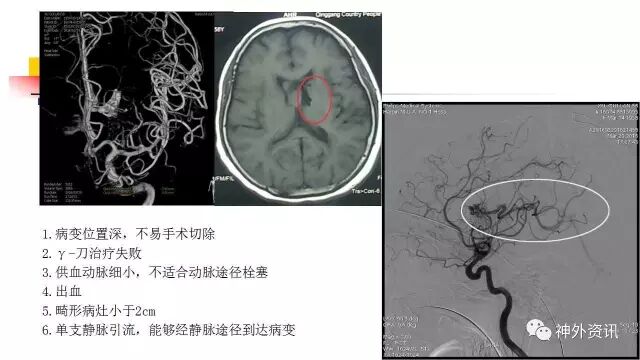

今天为大家分享的是《正海-妙术视界》第三十九期,由哈尔滨医科大学附属第一医院神经外科三病房主任史怀璋教授团队带来的国内首例“经静脉途径栓塞动静脉畸形”动态课件,相关文章亦已发表在2016年第12期的《International Neuroradiology》杂志,欢迎观看、阅读。